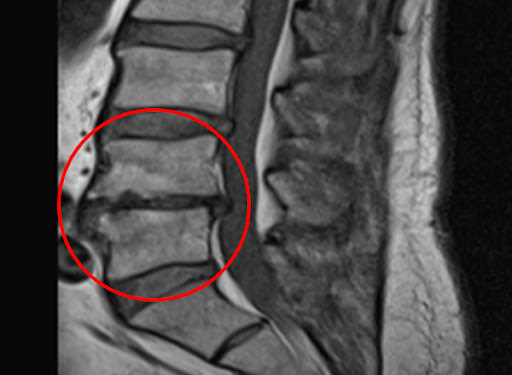

퇴행성 변화

가장 흔한 이유 중 하나는 퇴행성 변화입니다. 나이가 들어감에 따라, 척추의 디스크와 다른 구조물들이 시간이 지나면서 자연스러운 마모를 겪게 됩니다. 이로 인해 허리의 유연성과 지지력이 감소하게 되며, 척추관의 공간이 좁아지는 협착이 발생할 수 있습니다.

특히 중장년층에서 퇴행성 척추협착증이 빈번하게 발생하는 이유는 디스크의 수분 손실과 손상 때문입니다. 연세가 많은 분들은 특히 디스크의 수명이 줄어들고, 그로 인해 허리의 구조가 변형되며 신경이 압박을 받게 됩니다.